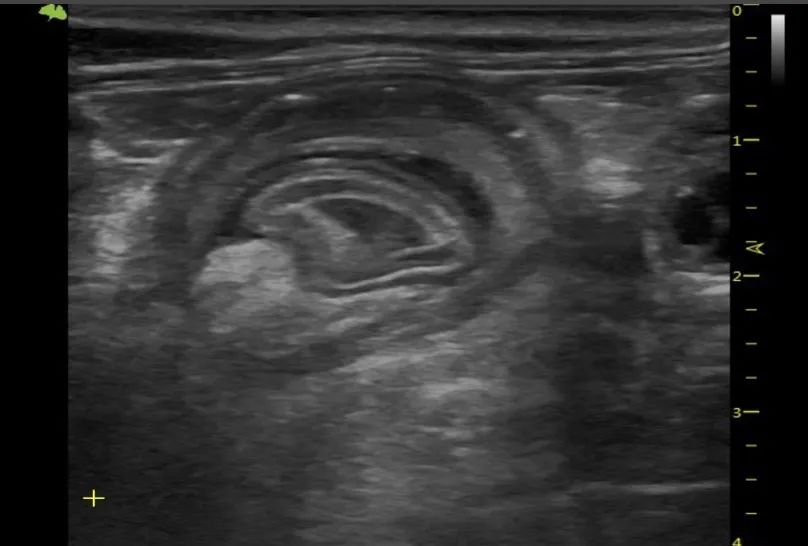

猫肠套叠在兽医文献中已有详尽记载。此报告为猫科动物肠套的病例报告,超声检查中确诊。描述猫肠套叠超声影像特征。

单发肠套叠在猫科动物中多发生于空肠-空肠轴或回盲结肠交界部,与本病例相似。本病例的特殊性在于少见肠套叠并发肠壁坏死,这凸显了延迟手术干预的高风险性,此风险已在宠主决定手术时充分告知。猫类相关报道中鲜少提及肠壁坏死,近期有文献报道一例犬肠道浆细胞瘤继发肠套叠。

本病例中,影像学检查显示套叠段分层结构清晰,提示原发病毒性肠炎病变可能性较高。此判断基于既往文献:猫肠套常与肠道肿瘤、寄生虫感染、线性异物、病毒性肠炎及腹部手术史相关。